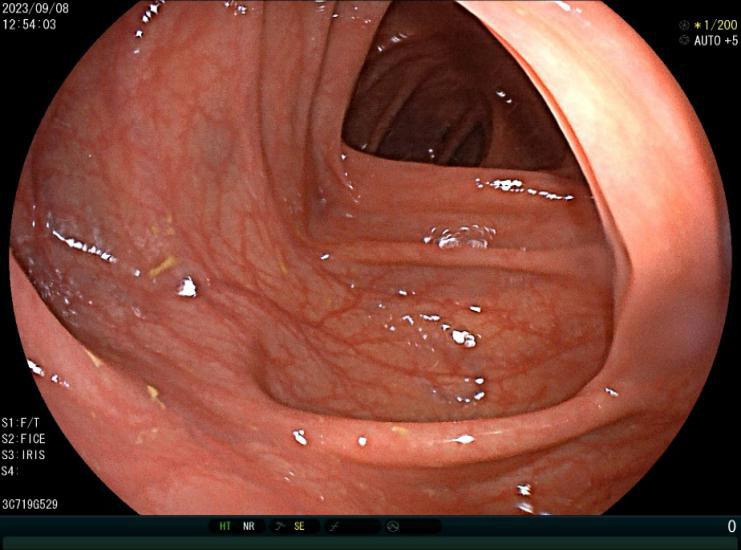

肠息肉是指突出于肠腔表面的隆起,在没有确定病理性质前统称为息肉,其发生率通常随年龄增加逐渐上升,病变部位以结直肠多发,与结直肠癌的发病有密切关系。

正常肠道

结肠息肉